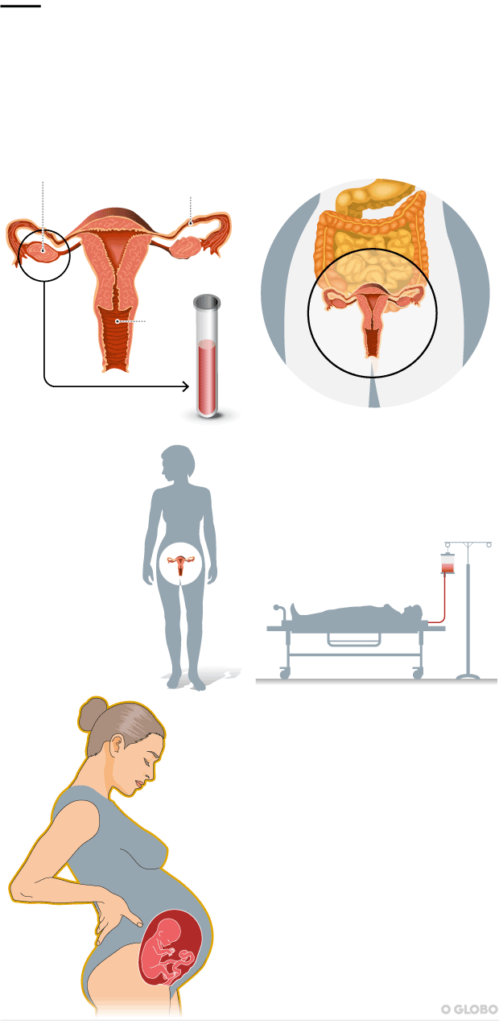

Uma menina paulistana prestes a completar 1 ano de idade é a primeira criança, no mundo, gestada por uma mãe que recebeu um útero de uma doadora falecida. O procedimento de sucesso ainda único no planeta foi realizado por uma equipe do Hospital das Clínicas da Universidade de São Paulo no ano passado, e agora está sendo oficialmente relatado em artigo publicado ontem no prestigiado periódico científico médico “The Lancet”.

Procedimento de sucesso ainda único no planeta foi realizado por uma equipe do Hospital das Clínicas da Universidade de São Paulo no ano passado, e agora está sendo oficialmente relatado em artigo publicado ontem no prestigiado periódico científico médico “The Lancet”. Foto: Divulgação

De volta ao país, os médicos brasileiros continuaram seus estudos com animais, mas também logo iniciaram as tratativas para fazer as primeiras operações em humanos, com uma diferença fundamental: os úteros viriam de mulheres falecidas. Até então, todas as poucas histórias de sucesso do procedimento, com o nascimento de crianças vivas, no mundo tinham sido de transplantes do órgão de doadoras vivas.